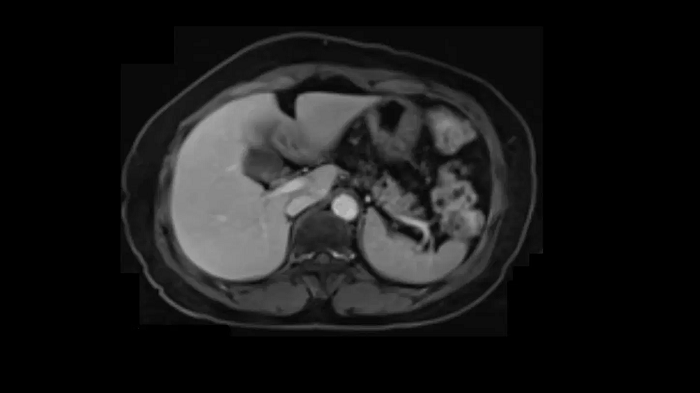

Compressed Sensing GRASP-VIBE

GRASP-VIBE Compressed Sensing for dynamic liver imaging in free-breathing patients who cannot hold their breath reliably.

- BioMatrix Spine 72

- Body 18

Image Credit: University Hospital Tübingen, Germany